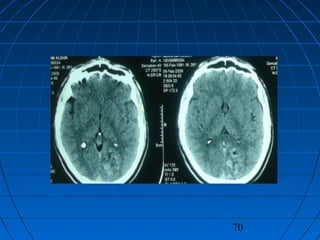

 İ.A.: 27 yaşında erkek hastaİ.A.: 27 yaşında erkek hasta

 BaşağrısıBaşağrısı

CERRAHİCERRAHİ

 Sol oksipital kranyotomiSol oksipital kranyotomi

 AVM’nin total rezeksiyonuAVM’nin total rezeksiyonu

 PostoperatifPostoperatif

Nörolojik Muayene ve DSA:Nörolojik Muayene ve DSA:

NormalNormal